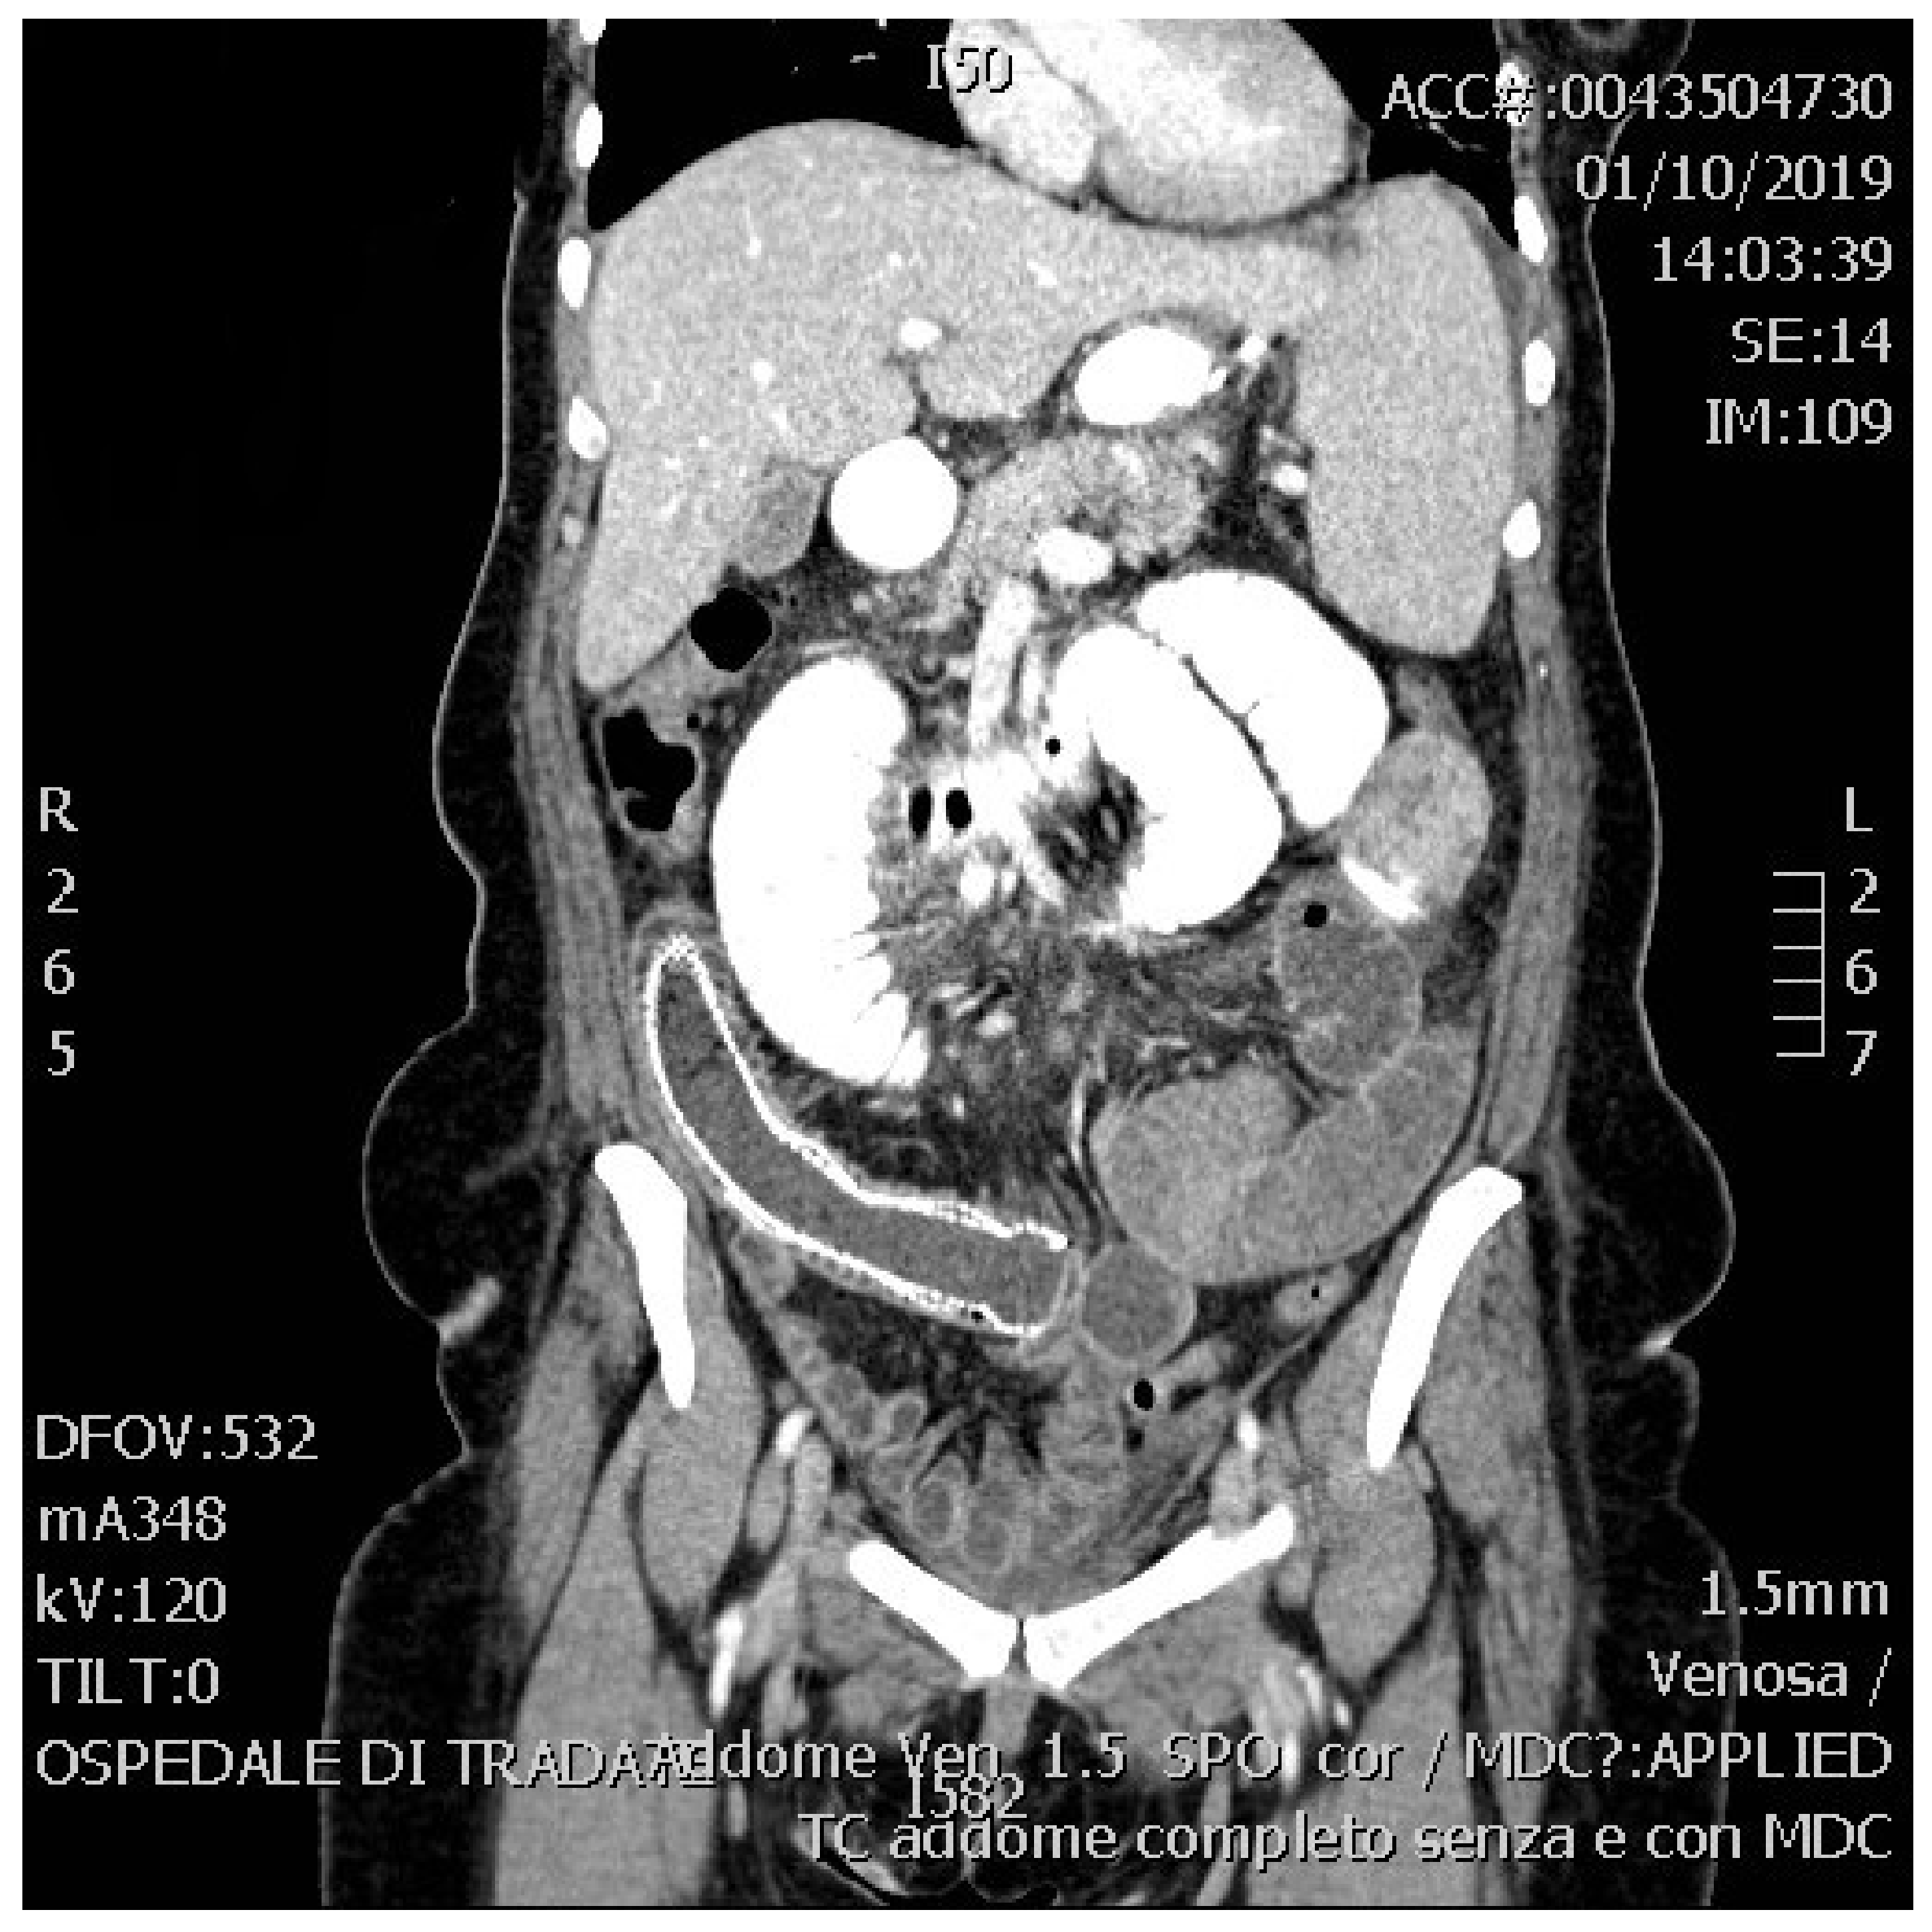

2. Presentation of the Case